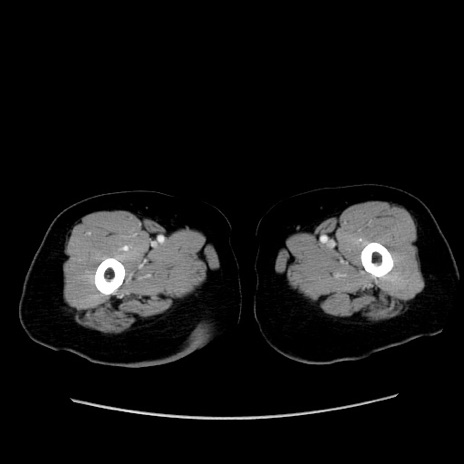

症例19(横断像)

【症例】80歳代女性

【主訴】下腹部痛

【現病歴】約8時間前より下腹部痛の出現あり、救急外来受診。

【既往歴】両側付属器切除

【身体所見】意識清明、下腹部正中に手術痕あり、その部位に一致して圧痛と反跳痛あり。腸蠕動音は亢進。

【データ】WBC 9300、CRP 0.15